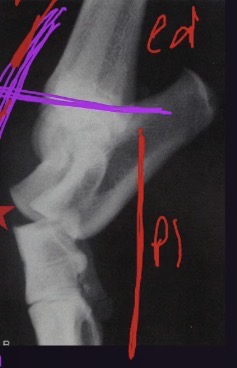

What view is this? What part of the joint can be seen?

stress radiography lateral view of tarsus

Stress applied to open up dorsal aspect of tarsus

Proximal intertarsal joint can be seen, it is unstable